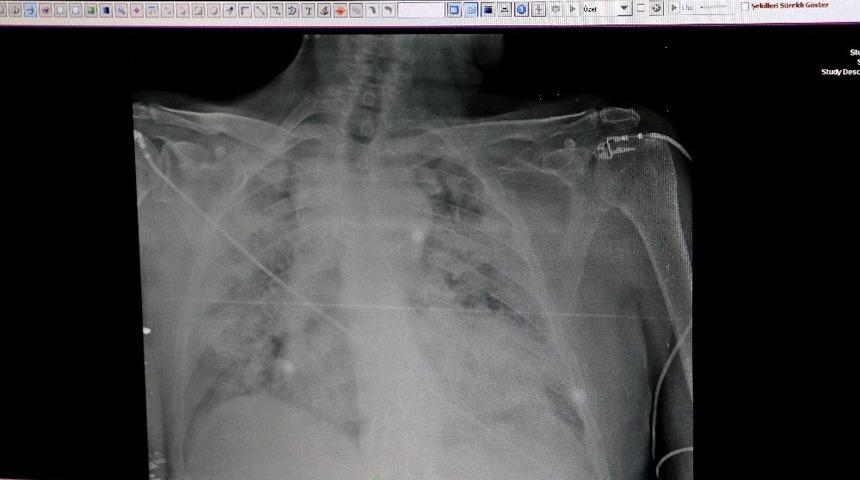

Çukurova Üniversitesi Tıp Fakültesi Hastanesi Göğüs Hastalıkları Ana Bilim Dalı Öğretim Üyesi ve Başhekim Yardımcısı Doç. Dr. Ezgi Özyılmaz, röntgenleri incelediği sırada normal sağlıklı bir akciğerde röntgen üzerinde siyah alanların olması gerektiğini ancak korona virüs hastalarının akciğerlerinin tamamen beyaz göründüğünü ve solunum güçlüğünü çekip makineye bağlı yaşadıklarını söyledi.

Korona virüsün akciğere indiği hastaların röntgen sonuçlarının kötü olduğunu belirten Özyılmaz, “Aslında teorik olarak daha önce gördüğümüz diğer mikroplara ve diğer nedenlere bağlı şeylere benziyor. Ancak bir takım nüans farklı var. Biz artık akciğer grafisinde görür görmez bunun korona virüs olup olmadığını hemen anlıyoruz” ifadelerini kullandı.